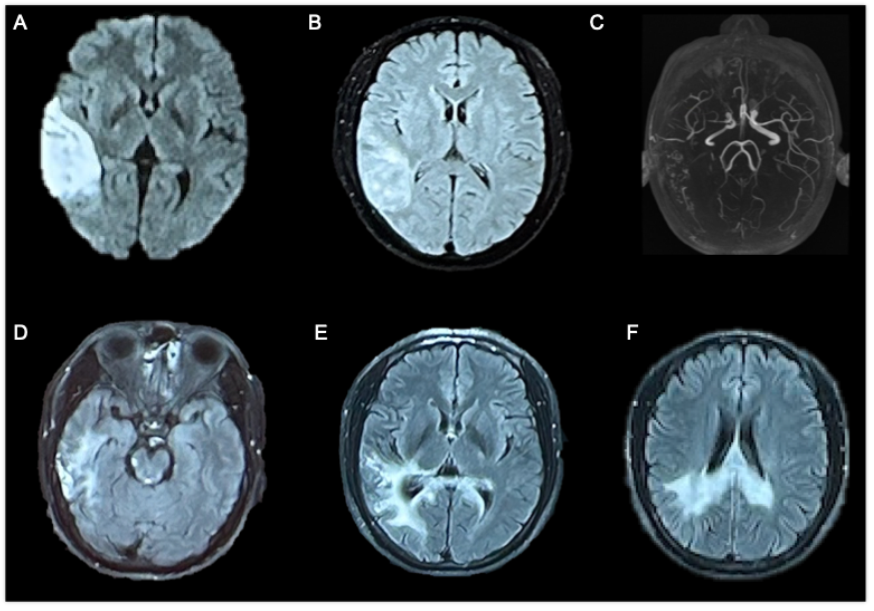

入院情况

图1 2023年6月头颅MRI结果(A~C);2024年8月头颅增强MRI结果(D~F)

(1)头颈CTA:多发动脉粥样硬化斑块。

(2)脑血管管壁增强MRI:右侧MCA M1重度狭窄,管壁不均匀增厚符合动脉粥样硬化。